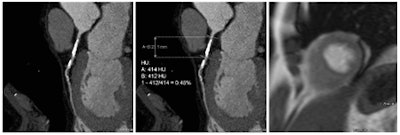

CCO "estimates the effect of a stenosis by measuring the Hounsfield contrast attenuation before and after a stenosis and corrects this for time using attenuation in the descending aorta," den Dekker explained. "This might substitute for functional imaging and can be added to the anatomical information of CCTA."

To assess the arteries, the group measured luminal CT attenuation values (in Hounsfield Units) in the proximal, middle, and distal segments of each coronary artery, using a dedicated workstation (Aquarius Intuition Edition, TeraRecon). Additional measurements (two proximal and two distal) were performed in arteries with significant (> 50%) lumen stenosis. CCO was then calculated by dividing coronary CT attenuation by descending aorta CT attenuation at equal level.

CCO was calculated by dividing the coronary measurements by the aorta attenuation at the same level, and the group calculated decreases in CCO across the coronary artery and across stenoses, comparing them with presence of inducible ischemia on APMRI using regression analysis.

The key to the study was the difference in CCO measurements across stenosis -- measurements that were significantly larger in patients with a perfusion defect causing hemodynamically significant stenosis (0.144 ± 0.112 m) compared with patients without perfusion defects (0.047 ± 0.104; p = 0.003).

But anatomically significant stenosis was another story: No CCO differences were seen between patients with anatomically significant stenosis (0.054 ± 0.116) and those without (0.052 ± 0.101; p = 0.89).

"When we measured the contrast attenuation before and after a significant stenosis there was no difference in those without ischemia, while a decrease [in contrast attenuation] was seen in stenosis with hemodynamic significance," den Dekker said. "There was also ... a difference in CCO between stenosis causing ischemia compared to those that do not cause ischemia -- while on CCTA there was no difference [between] anatomically significant and nonsignificant stenoses."